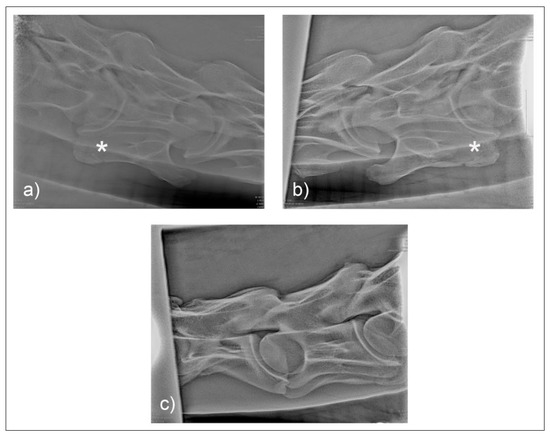

Figure 9. The radiographic images of the 30° dorsal to ventral oblique left (a) and right (b) of C6 in horse M2 and the laterolateral view (c) of horse M2 with bilateral morphologic variation of C6 and transposition on to C7 (*). (Note example of marker dorsal to C5 transverse process).

3. Results

Two horses (F1, M1) presented with unilateral morphological variations of C6. In horse F1, C7 was also affected, which has been noted to be more common in females [12]. Postmortem examination of horses M1 (Figure 5 and Figure 6) and F1 (Figure 7 and Figure 8) revealed morphological variations consistent with radiographic images and confirming the diagnosis of ECCMV in both cases. The remaining horse (M2) presented with a symmetrical bilateral variation of C6 (Figure 9), with transposition on to C7 visible on the radiographs (Figure 9c). The morphological variations can be appreciated in the ventral and cranial views of the bones, as well as the 30° oblique views (Figure 6 and Figure 8).

Two common operator and reviewer errors are identification of a false bilateral morphologic variation of C6 when actually imaging the normal C5 vertebrae. Conversely, diagnosing the bilaterally absent ventral laminae on C6 as normal is another common mistake (Figure 10c). It should be noted that the caudal ventral tubercles of C6 have separate centers of ossification that may be misdiagnosed as fractures [7]. Asymmetry of the articular process joints in the cervical spine may make true laterolateral image capture difficult [7]. The laterolateral images of C6, along with the dorsal to ventral oblique images, are key to interpreting the symmetry, length, and shape of the lamina (Figure 4c). Field radiographs make the assessment of transposition on to C7 difficult in some cases. The transposition may be visible less commonly on the oblique views (Figure 9b) depending on the shape and position of the transposition [11]. Transposition on to C7 is more commonly seen on the laterolateral views and is usually seen below the transverse processes [11]. In some cases, the transposition may be seen on the oblique view (Figure 9b). Some three-dimensional alterations are so severe that misinterpretation of the morphology on C7 can occur (Figure 8c). This highlights the need for more detailed diagnostic assessment in these cases. Spinal cord compression by an asymmetrical canal, articular process periarticular bone formation and extent of intravertebral foramina compression cannot be assessed by radiography alone [10]. The study of the prepared vertebra in three dimensions is key to understanding the potential alterations in regional biomechanics.